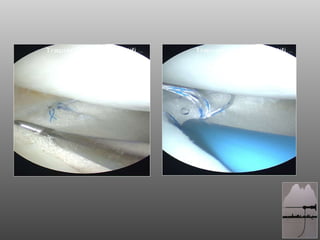

DOPO 1aa

CONCLUSIONI SALVIAMO IL MENISCO !! LO SCAFFOLD MENISCALE E’ LA MIGLIORE RISPOSTA AL GINOCCHIO PARZIALMENTE MENISCECTOMIZZATO ACCURATA SELEZIONE DEL PAZIENTE E CORRETTA TECNICA CHIRURGICA SERVONO F.U. PIU’ LUNGHI  RIGENERAZIONE DEL MENISCO CON FATTORI DI CRESCITA

CONCLUSIONI SALVIAMO ILMENISCO !! LO SCAFFOLD MENISCALE E’ LA MIGLIORE RISPOSTA AL GINOCCHIO PARZIALMENTE MENISCECTOMIZZATO ACCURATA SELEZIONE DEL PAZIENTE E CORRETTA TECNICA CHIRURGICA SERVONO F.U. PIU’ LUNGHI RIGENERAZIONE DEL MENISCO CON FATTORI DI CRESCITA